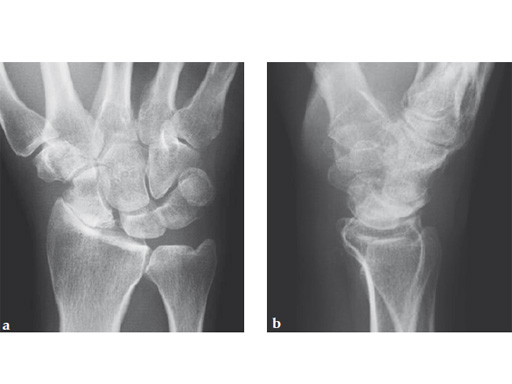

Fig 1ab Preoperative x-rays. Note the carpal collapse a a b nd DISI deformity.

Fig 1ab Preoperative x-rays. Notice the midcarpal joint destruction and the DISI deformity of the lunate.

Midcarpal fusion involves excision of the scaphoid in order to address the painful radioscaphoid osteoarthritis. The midcarpal joint needs to be stabilized due to potential pain and arthritis depending on the stage of SLAC/SNAC. Stabilization is performed by arthrodesis of the lunate, capitate, hamate and triquetrum, subsequently named a 'four-corner fusion.' As the radiolunate joint is usually spared from arthritic changes, there is normally sufficient and pain-free residual motion between the lunate and the radius.